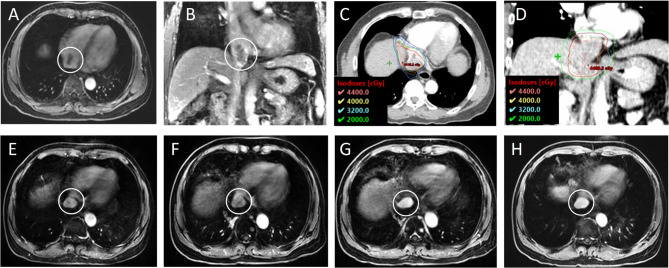

立体定向体放疗治疗肝细胞癌伴右心房肿瘤血栓的疗效和安全性:一项双中心回顾性评价。

Efficacy and safety of stereotactic body radiotherapy for hepatocellular carcinoma with tumor thrombus in right atrium: a two-center retrospective review.